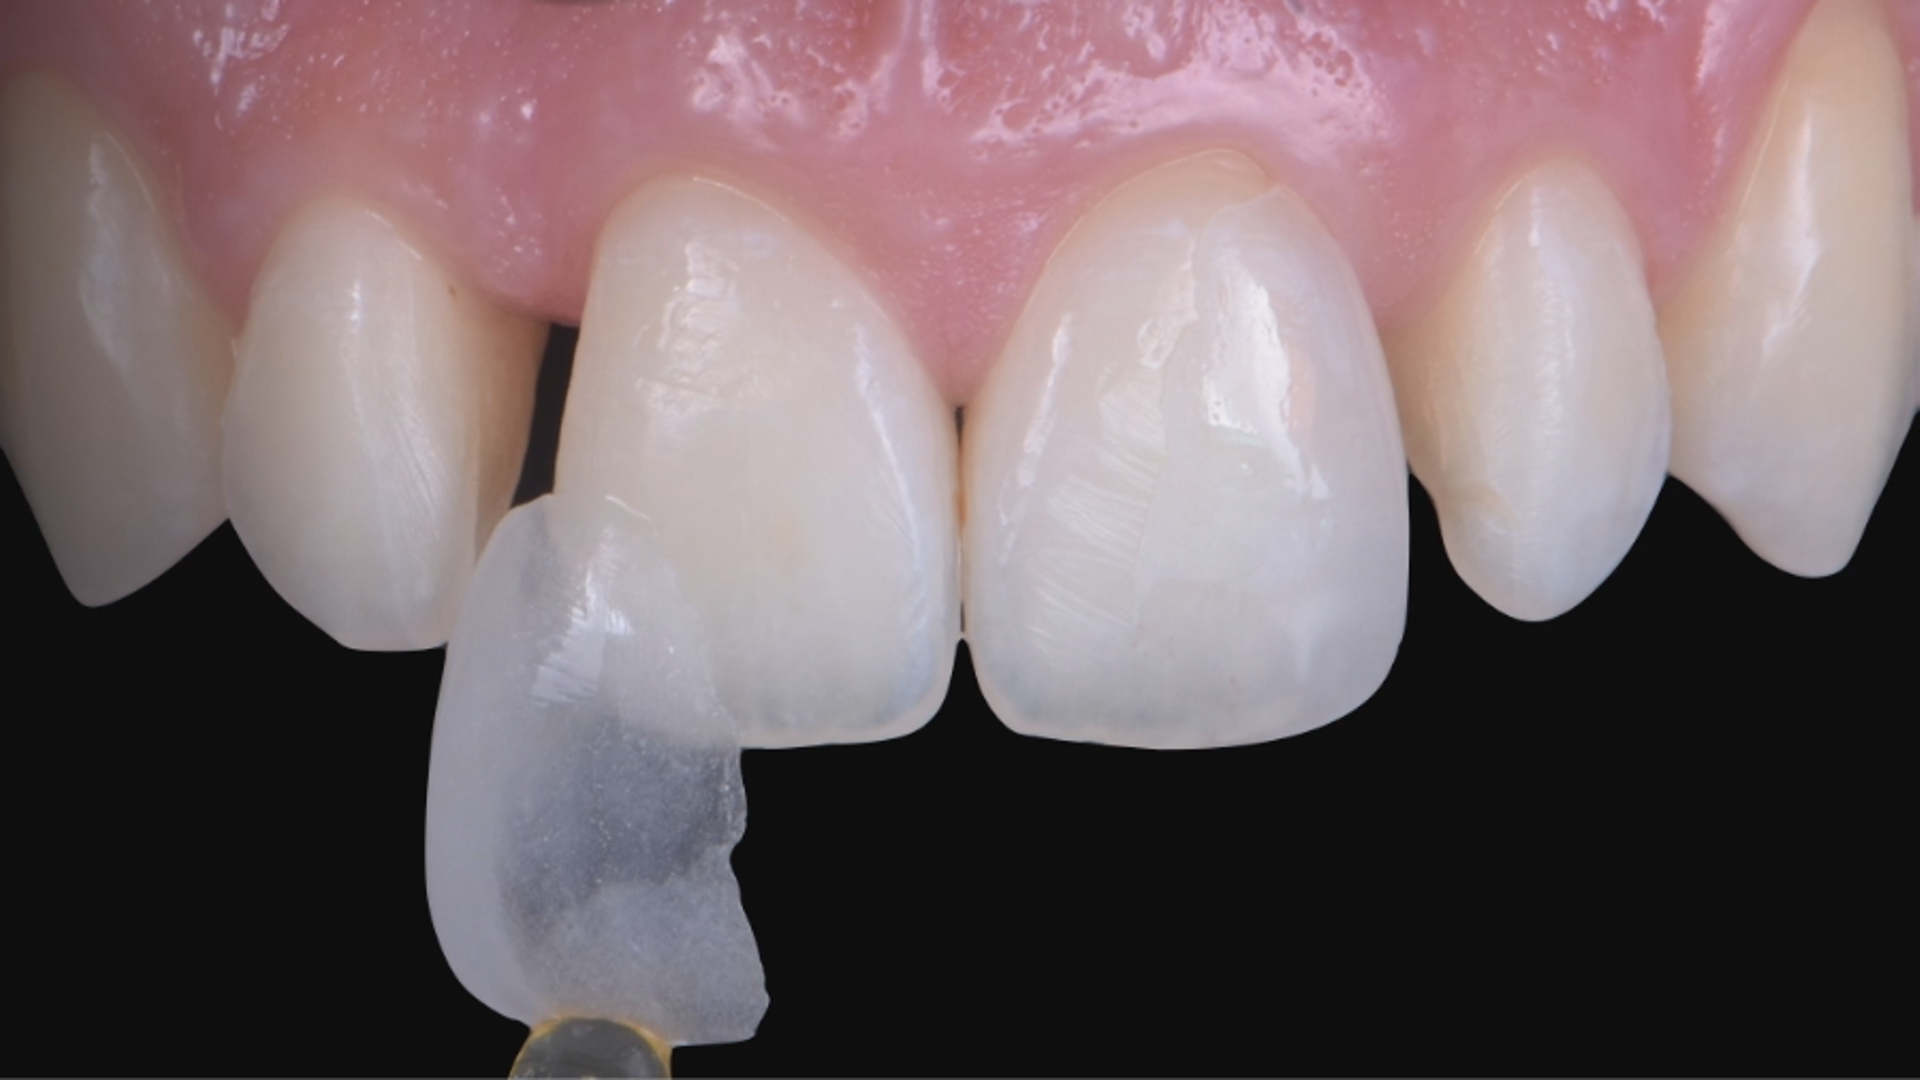

MIPP 0: clinical cases and No-prep veneers procedures

Clinical case - MIPP 1: conventional buccal veneers procedures

MIPP 2: the new concept behind Full-Veneers to optimise aesthetics and functionality

MIPP 2B: clinical case of Full-Veneers in openbite with preserved enamel tooth structure

MIPP 2: MIPP 2A and MIPP 2B combined technique